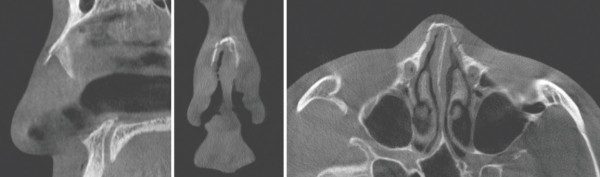

CT상 비골의 복합 골절이 관찰된다. 측면에서는 비골의 함몰, 정면과 밑면에서는 비골의 좌측 이동과 동반된

비중격의 골절을 확인할 수 있다. 이러한 비골과 비중격 골절을 방치한다면 안장코 변형과 코막힘을 초래할 수 있다.